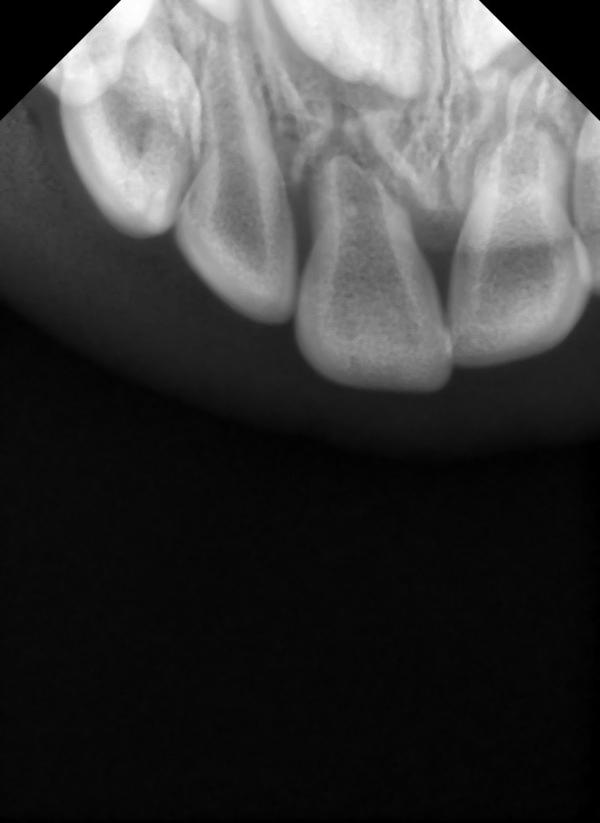

Но снимок недавно делала,у вас по середине зуб? Случайно не киста? Просто такое же было около зуба темное в костной ткани

Нет ребёнок зубом молочным ударился , и подшатывается, в клинике говорят удалять зуб, а его никак не беспокоит он , вот и я собираю мнения врачей

А темное это наверно сгусток крови